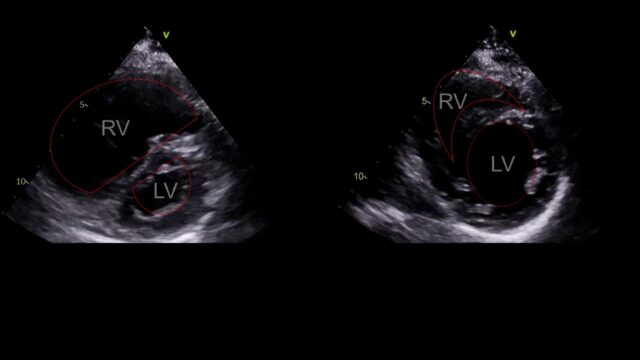

These images are all from a young female with high risk PE with pre and post lysis images. In a revolution of AI assited imaging they now come with added labels…

This is PSSAX view. In a life threatening PE the RV enlarges, the right sided pressures rise and the interventricular septum loses its roundness and becomes flat. This is the D sign you might here of. Like a capital D tilted over slightly.

The apical 4 chamber view. The RV should be smaller than the LV, if it’s a lot bigger something is wrong. This view also allows us to look at something called TAPSE basically how much does this little nubbin at the tricuspid valve move up and down. If it moves up and down loads that’s good, if only a little that’s bad.